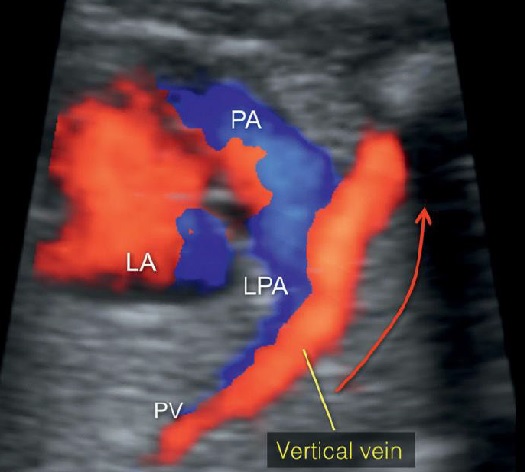

Hình 12: Hình ảnh thai nhi có bất thường hồi lưu tĩnh mạch phổi toàn phần thể trên tim (supracardiac) (A) Sơ đồ 4 tĩnh mạch phổi đổ vào tĩnh mạch hợp lưu (confluent vein); (B) hình ảnh mặt cắt tương ứng theo đường màu ở sơ đồ (A). Các mũi tên nhỏ ở A và B thể hiện tĩnh mạch phổi (PV) đổ vào tĩnh mạch hợp lưu (confluent vein - mũi tên lớn) sau đó đổ vào tĩnh mạch dọc (Vertical vein - vv - mũi tên rỗng) rồi đổ vào tĩnh mạch chủ trên (SVC) thay vì đổ vào nhĩ trái (LA). Hình ảnh 3D Doppler tương ứng (hình 13).

Hình 13: Siêu âm 3D Doppler màu của lồng ngực thai nhi có TAPVR – type I. Hình ảnh tĩnh mạch phổi hội lưu về tĩnh mạch dọc sau đó kết nối với tĩnh mạch cánh tay đầu (brachiocephalic vein) chứ không phải đổ vào tâm nhĩ trái (LA). PV: tĩnh mạch phổi; PA: động mạch phổi.